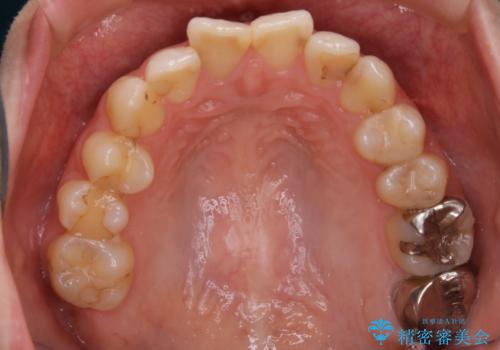

- 前歯のガタつきと噛み合わせの改善を主訴に初診来院され、審査の結果マウスピース装置による非抜歯での矯正を行うこととなりました。

元々の顎骨や口腔・歯槽骨が小さく、どうしても歯が並びきらない状況になっていました。マイクロインプラントという固定源からゴムかけを行うなど、補助装置を活用しながら臼歯部を順番に遠心方向(奥)に移動させていくことで抜歯をしなくても歯が並ぶよう計画を立てました。

マイクロインプラントとIPR

歯を並べるスペースを作るために、歯の遠心移動と歯列の拡大、歯自体を少しだけ小さく削る(IPR)という方法を複合的に組み合わせて配列を行いました。遠心移動用のゴムかけにはマイクロインプラントという小さいネジを用いて骨に直接固定源を求めました。